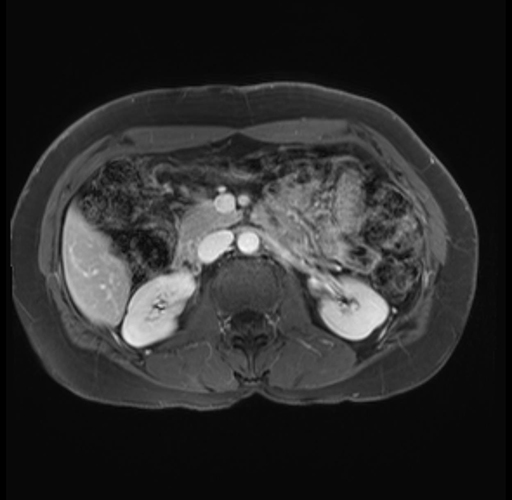

Imaging Analysis

Look through the patient's CT scan to identify any areas of concern for the necessary procedure.

Based on your CT findings, which issue(s) are present and would give reason for "planned slowing down moment(s)" in this case?

Considering a standard distal pancreatectomy procedure, what step(s) of the operation would you do differently in this case?